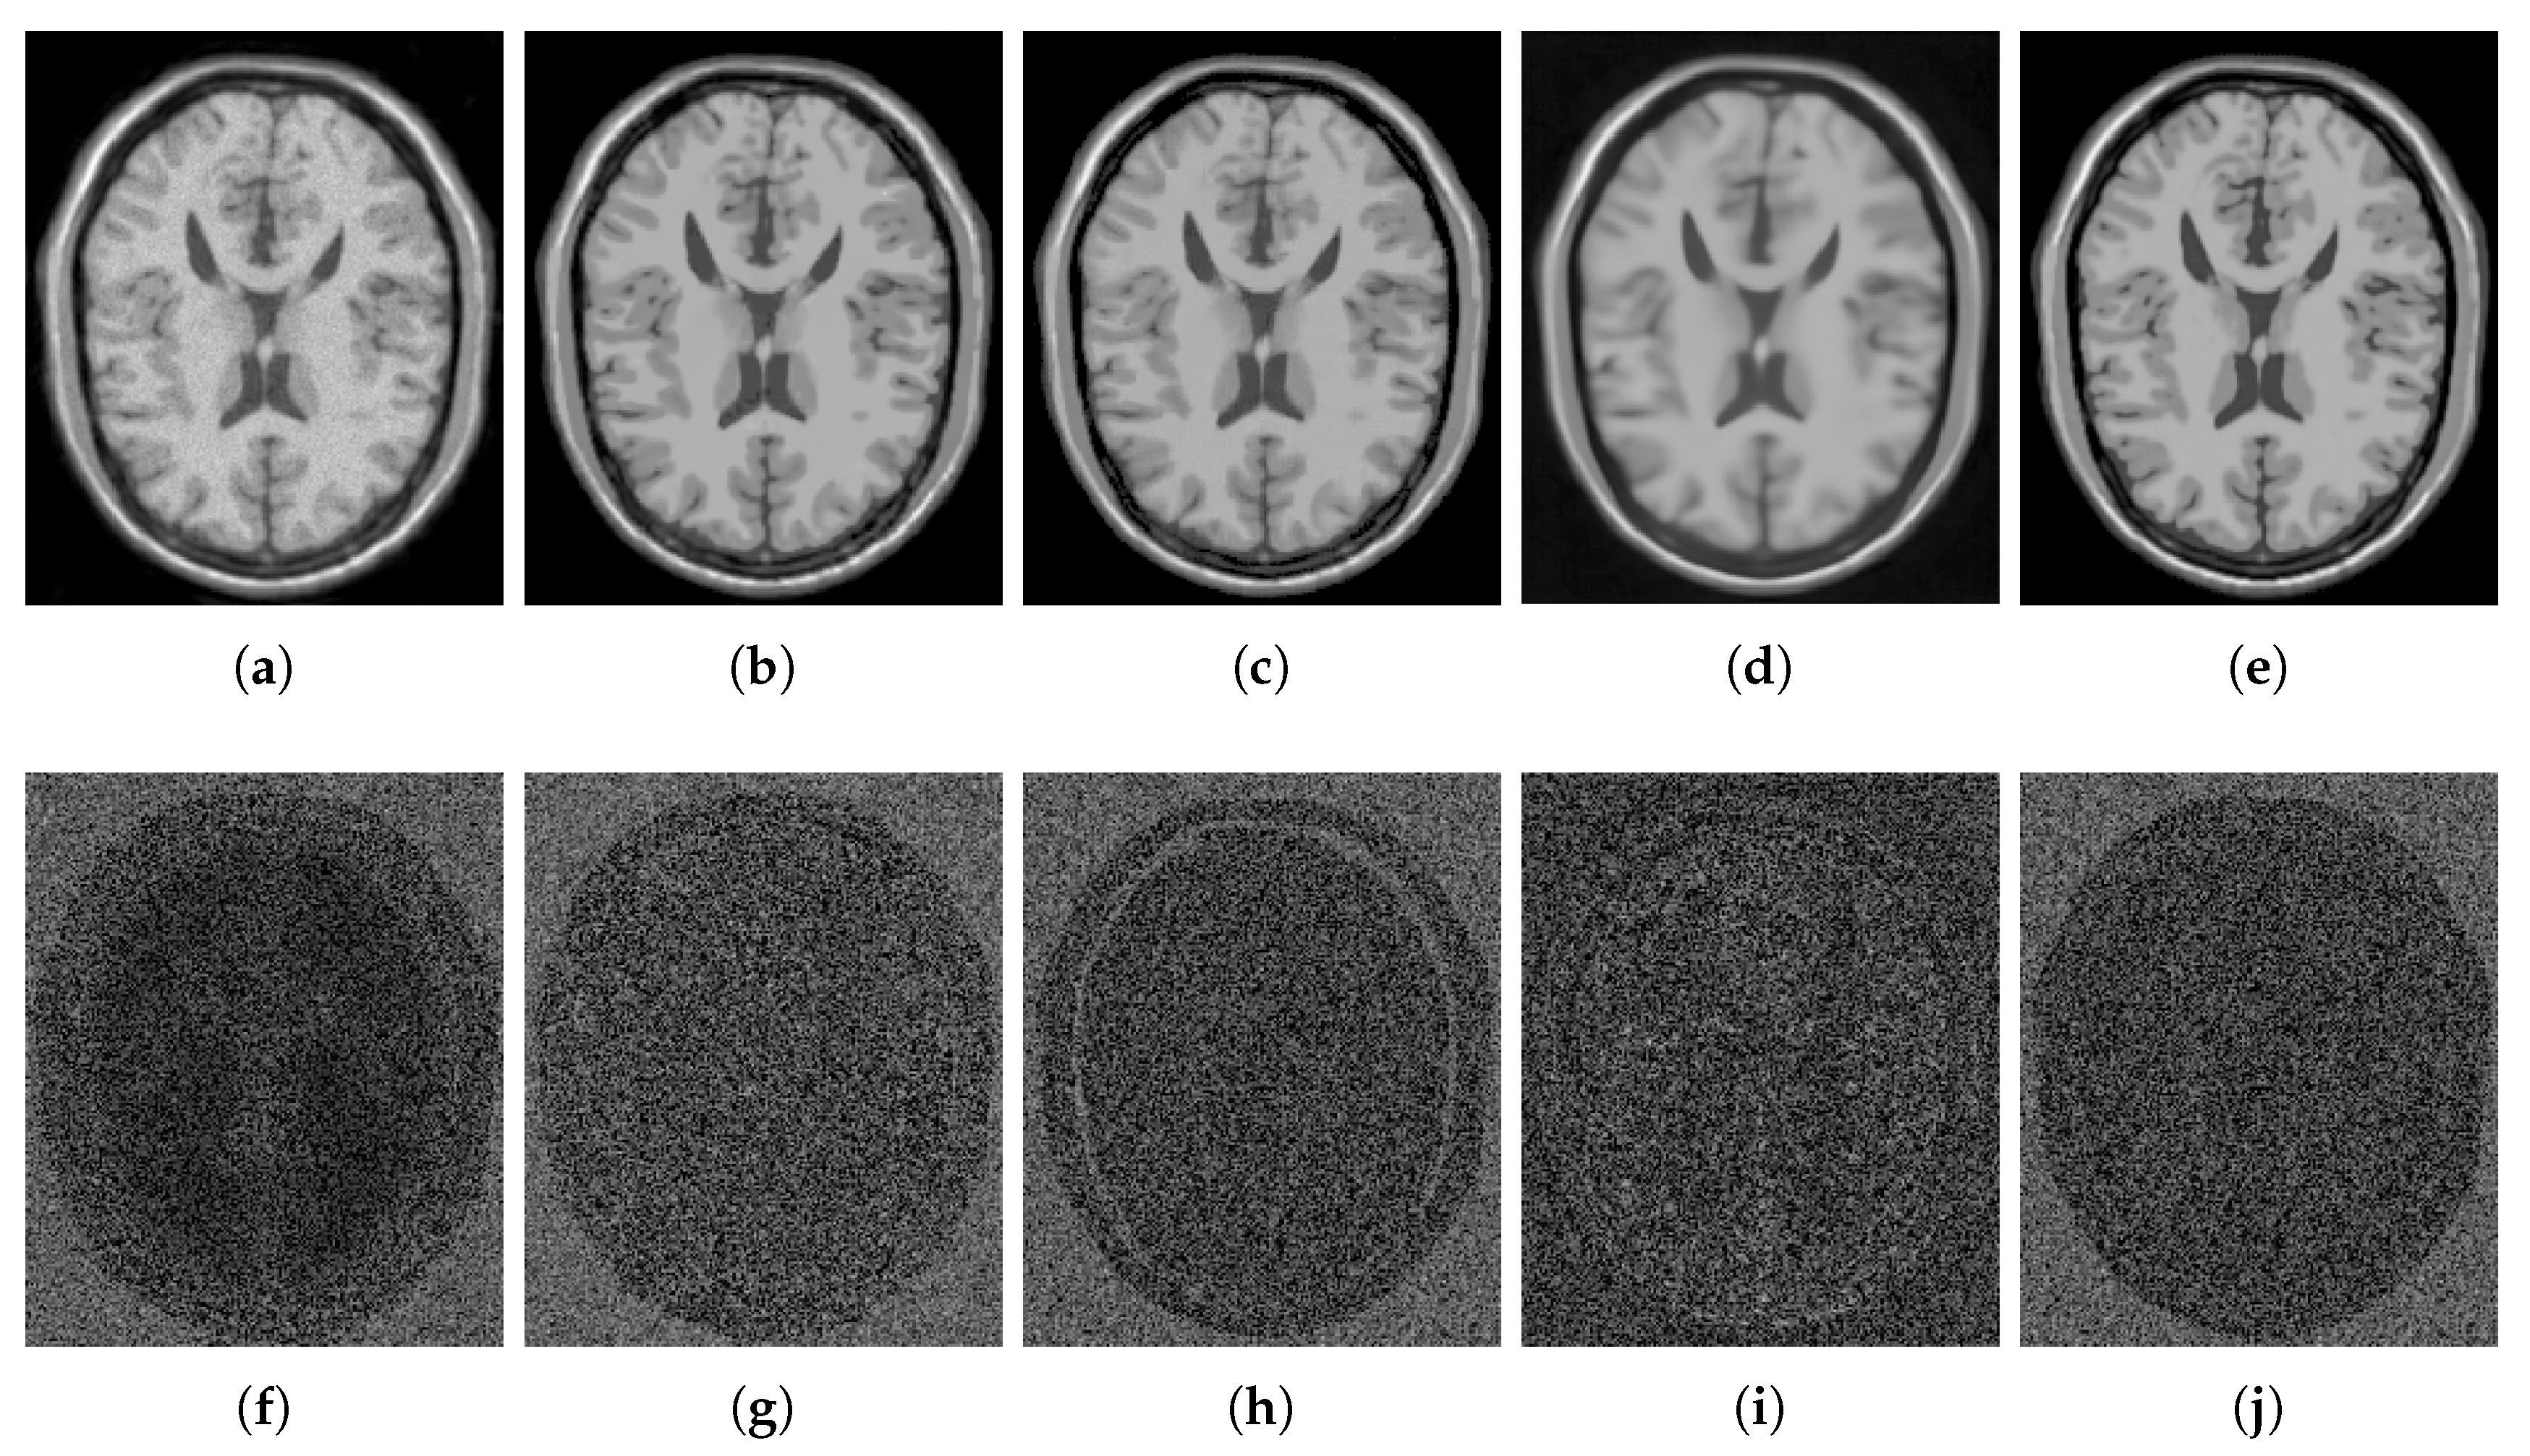

4.2.1. Synthetic Data

4.2.2. Real Data